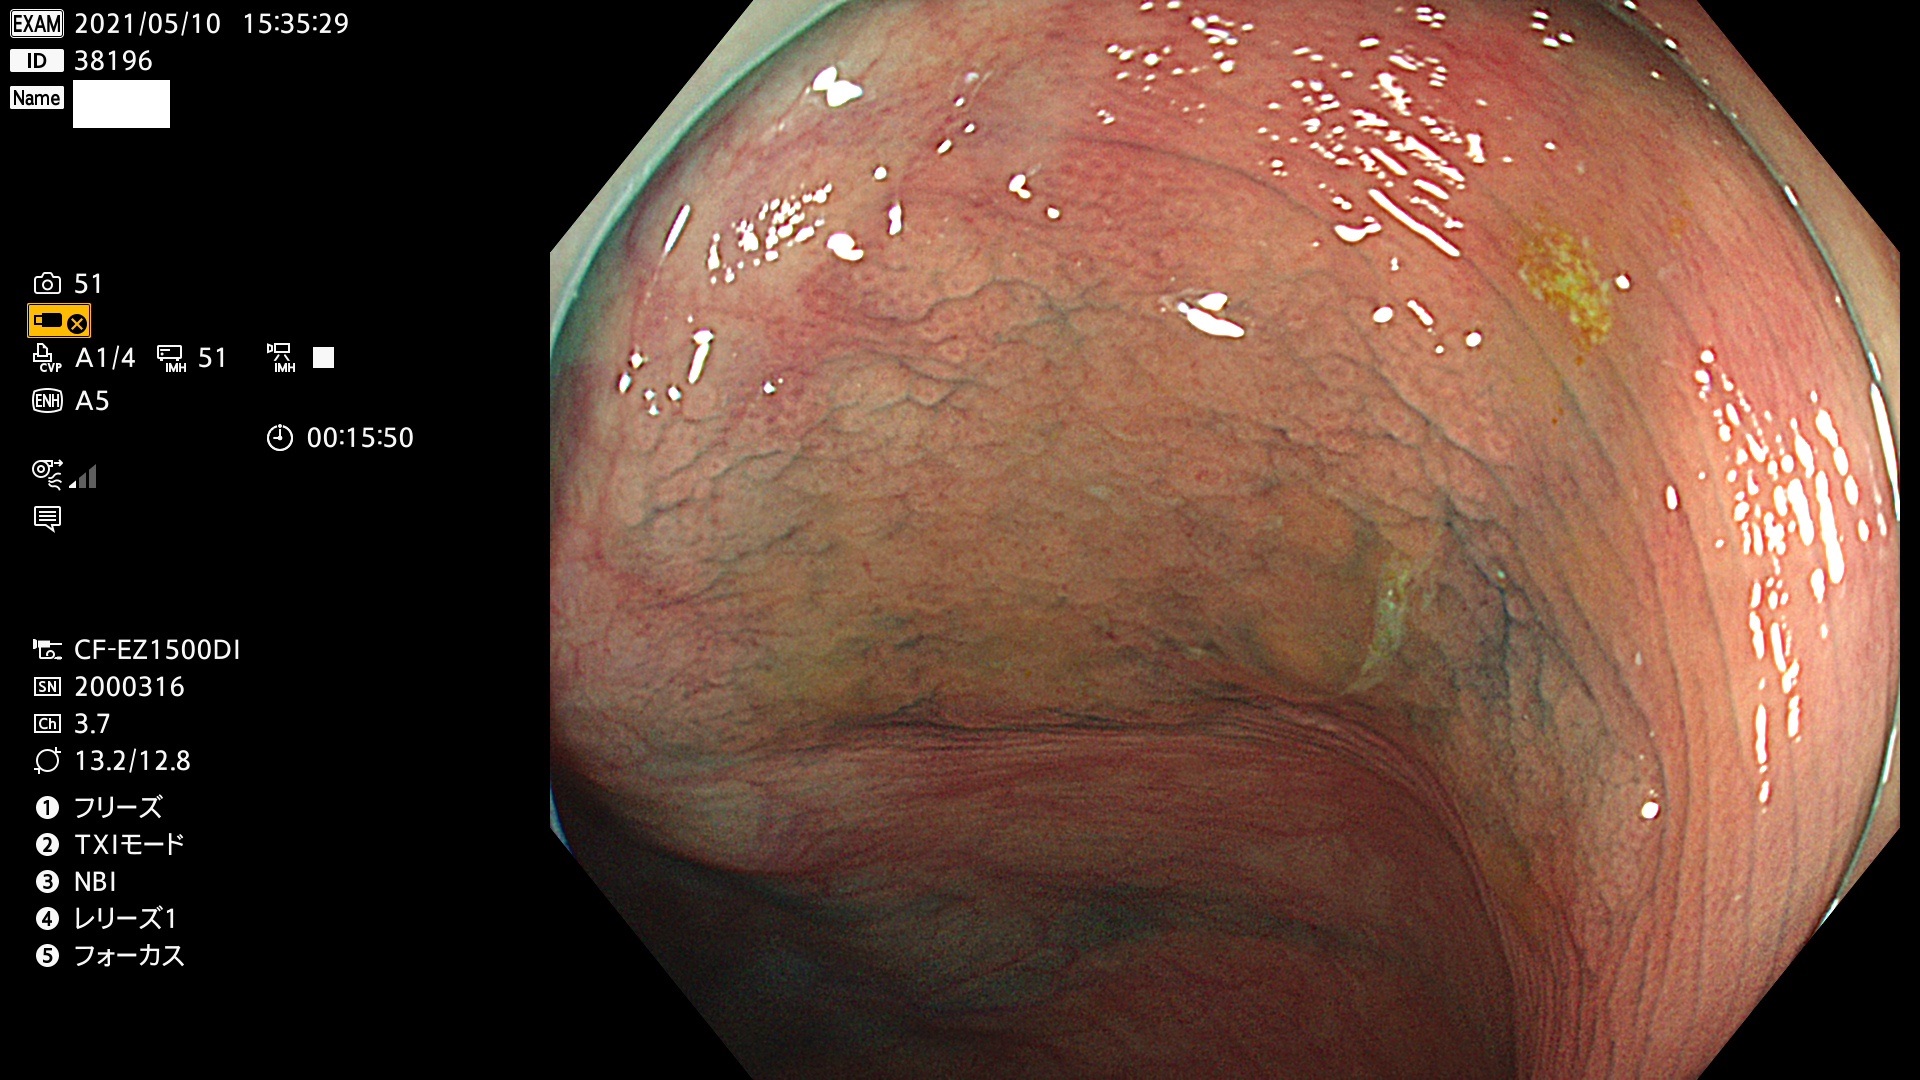

腺腫発見率 72 % (カルテ番号 38100〜38199の100名の方の検査結果で集計)大腸癌検診最新情報

以下のカルテ番号の方に腺腫(Adenoma,Group3〜5)が見つかりました(集計法)

38101 38103 38104 38106 38107 38108 38109 38110 38111 38112 38113 38114 38115 38117 38118 38122 38123 38124 38125 38126 38127 38128 38130 38131 38132 38135 38137 38138 38140 38141 38142(SSAPのみ) 38143 38144 38145 38146 38147 38148 38149 38150 38151 38152 38153 38154 38157 38158 38160 38161 38162 38164 38165 38166 38167 38168 38169 38172 38176 38177 38178 38181 38182 38183 38184 38187 38189 38190 38191 38192 38193 38194 38195 38196(SSAPのみ) 38198

発見困難で危険性の高い平坦型病変(上記100名より抽出) ![]()